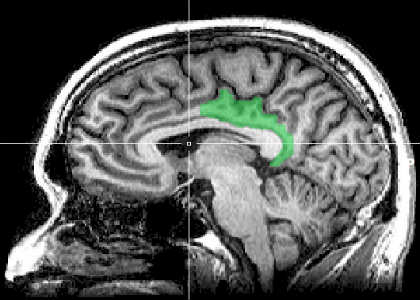

“Subjects with higher pain intensity ratings had less grey matter in brain regions that contribute to internal thoughts and control of attention,” said Nichole Emerson, B.S., a graduate student in the Coghill lab and first author of the study. These regions include the posterior cingulate cortex, precuneus and areas of the posterior parietal cortex, she said.

The posterior cingulate cortex and precuneus are part of the default mode network, a set of connected brain regions that are associated with the free-flowing thoughts that people have while they are daydreaming.

“Default mode activity may compete with brain activity that generates an experience of pain, such that individuals with high default mode activity would have reduced sensitivity to pain,” Coghill said.

Areas of the posterior parietal cortex play an important role in attention. Individuals who can best keep their attention focused may also be best at keeping pain under control, Coghill said.